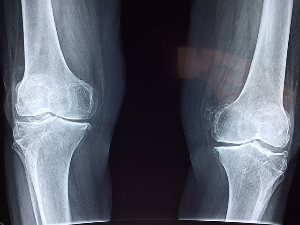

콘드로이친은 주로 관절을 둘러싼 연골을 구성하는 물질로, 젊었을때는 체내에서 잘 생성되지만 연령이 증가하면서 체내에서 합성하는 능력이 저하되어, 중년이 되면 몸에서 필요한 양의 5% 밖에 생성되지 않는다고 합니다. 콘드로이친이 결핍되면 연골의 탄력이 떨어지고 닳을 수 있기 때문에 하루 1200mg의 섭취가 권장됩니다.콘드로이친 1200mg 효능

연구에 따르면 콘드로이친은 관절 건강에 상당한 효능을 보일 수 있다고 합니다. 콘드로이친 1200mg의 효능으로는 관절 통증을 줄이고, 관절 기능을 향상시키며, 골관절염의 진행을 늦추는 데 효과가 있다고 합니다.

콘드로이친 1200mg은 연골에 물을 끌어들여 충격 흡수 능력을 높이고, 이를 통해 관절 건강을 증진시킨다고 알려져 있습니다.

1. 콘드로이친 1200mg 효능 관절 통증 완화

콘드로이친 효능 콘드로이친 1200ng의 주요 이점 중 하나는 관절 통증을 완화시킬 수 있다는 점입니다. 몇몇 연구들은 콘드로이친 1200mg이 많은 사람들이 겪고 있는 관절염인 골관절염으로 인한 고통을 줄이는데 도움을 줄 수 있다는 것을 보여주었습니다. 콘드로이친 1200mg은 연골을 지지하고 기능을 향상시킴으로써 관절의 염증과 불편함을 줄이는데 도움을 줄 수 있습니다.

3. 콘드로이친 1200mg 효능 골관절염 진행 완화

게다가, 콘드로이친은 관절염의 진행을 늦추는 것으로 발표되었습니다. 관절염의 특징으로, 연골의 퇴화는 시간이 지남에 따라 관절 손상과 악화로 이어지게 되는데 연구에 따르면 콘드로이친은 연골을 보호하고 보존하는 데 도움을 줄 수 있으며, 잠재적으로 퇴행 과정을 늦추고 관절 건강을 유지할 수 있습니다.